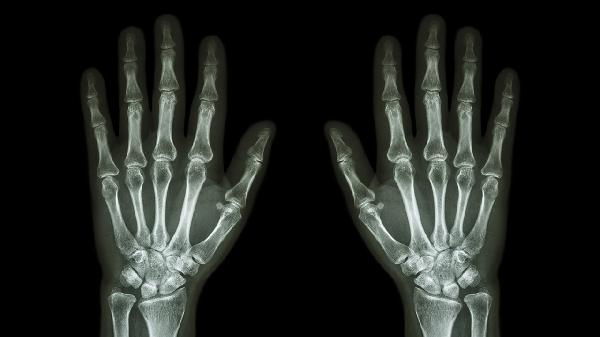

掌骨骨折怎么护理 从四个方面护理好骨折掌骨

掌骨骨折可通过固定制动、冰敷消肿、药物止痛、功能锻炼等方式护理。掌骨骨折通常由外伤、骨质疏松、暴力打击、运动损伤等原因引起。

护理期间需保持高钙饮食,每日摄入300ml牛奶或等量豆制品,适量补充维生素D促进钙吸收。戒烟限酒避免影响骨骼愈合,睡眠时用枕头垫高患肢。定期复查X线观察骨痂形成情况,若6周后仍存在异常活动需考虑二次手术干预。